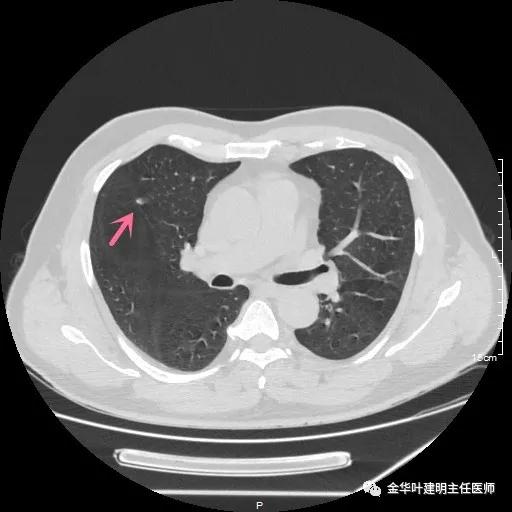

患者年纪虽然不大,但合并存在肾病综合征、高血压、高血压性心脏病、高脂血症、动脉硬化伴斑块、甲状腺结节、前列腺增生及脂肪肝、糖耐量异常等一系列问题。关键是后续需要大剂量激素治疗。下面是其2019年9月份的平扫CT图像,层厚1.2毫米:

可见是右肺中叶的微小实性结节,不规则形,密度甚高,无明显磨玻璃成份,也非圆形或类圆形,明显是一纤维增生性质的结节,肯定是可以随访观察的。当然去年也没报需警惕,或叫我们胸外科会诊。但再来看今年的图像,也是薄层扫描,层厚同样是1.2毫米: